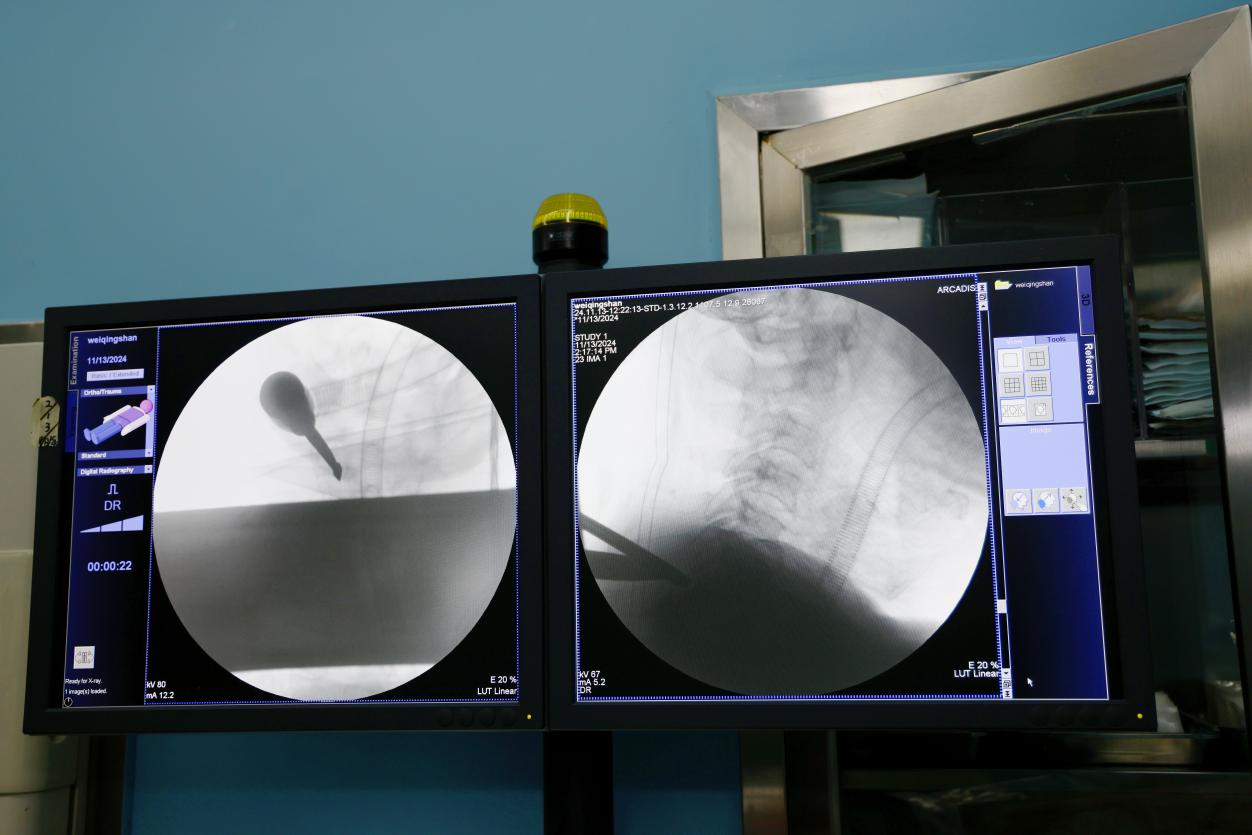

近日,北京中醫(yī)藥大學(xué)東方醫(yī)院骨科順利開展了東方醫(yī)院首例單側(cè)雙通道脊柱內(nèi)鏡(UBE)頸椎間盤髓核切除手術(shù),標(biāo)志著醫(yī)院在脊柱微創(chuàng)治療領(lǐng)域邁出了重要一步。

手術(shù)的患者是一名65歲的男性,因為頸6-7椎間盤突出,脫出的髓核壓迫了相應(yīng)神經(jīng)根,引發(fā)左肩及左上肢劇烈疼痛和麻木感,活動明顯受限,嚴(yán)重影響了生活質(zhì)量。為盡快緩解患者的疼痛,早日康復(fù)恢復(fù)正常生活,骨科主任李運(yùn)海與副主任醫(yī)師王亞非在對患者進(jìn)行全面且詳細(xì)的身體檢查和綜合評估后,決定采取“單側(cè)雙通道脊柱內(nèi)鏡下頸椎間盤髓核切除術(shù)”微創(chuàng)手術(shù)治療方案。因為頸椎周邊分布有許多重要的血管和神經(jīng),手術(shù)操作復(fù)雜,風(fēng)險大。然而,經(jīng)過骨科團(tuán)隊的精心準(zhǔn)備和緊張有序的手術(shù)操作,患者術(shù)后疼痛癥狀消失,目前已順利出院。

單側(cè)雙通道內(nèi)鏡技術(shù)(UBE)是一項新興的脊柱微創(chuàng)技術(shù),該技術(shù)通過兩個小切口建立兩個獨(dú)立的通道,一個用于內(nèi)鏡觀察,另一個用于手術(shù)操作。這種設(shè)計使得手術(shù)視野更清晰,操作更靈活。UBE技術(shù)適應(yīng)癥廣泛,包括幾乎所有節(jié)段的頸椎、胸椎、腰椎,以及大部分退行性疾病如椎間盤突出、椎管狹窄、椎體滑脫等。